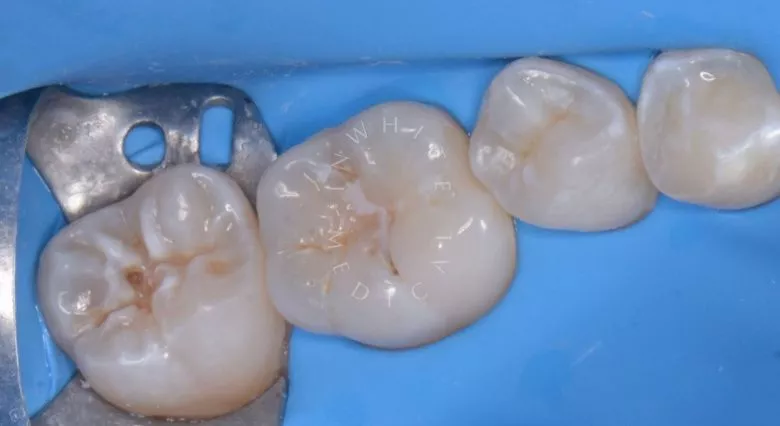

Лечение под наркозом - установка коронок и профессиональная гигиена у детей

етская стоматология лечение под наркозом. Лечение под наркозом - установка коронок и профессиональная гигиена у детей - до процедуры

етская стоматология лечение под наркозом. Лечение под наркозом - установка коронок и профессиональная гигиена у детей - после процедуры